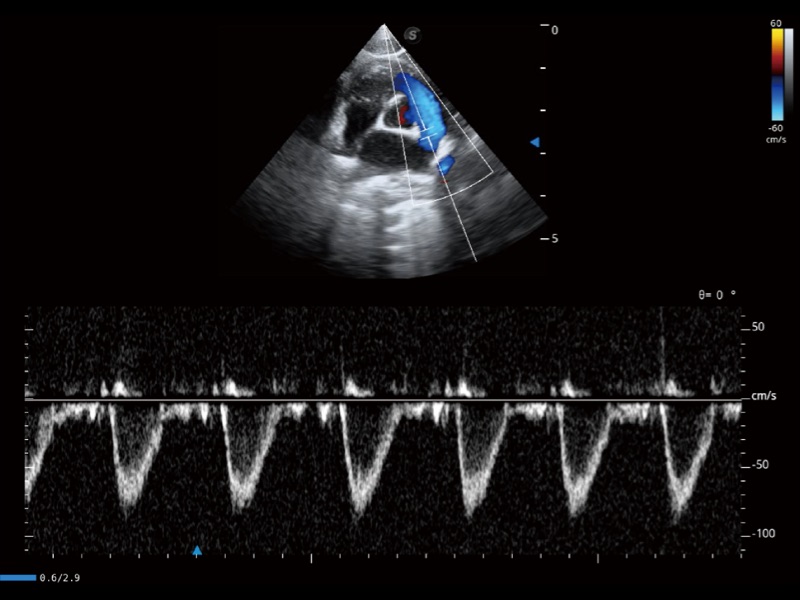

优异的基础图像

(猫)肺动脉血流频谱

(犬)左室长轴血流